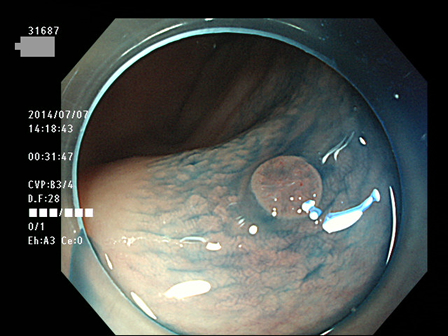

31600 31601 31603 31604 31606  31607 31610 31611 31612 31616 31623 31624 31625 31627 31630 31631 31632 31638 31639 31640 31641 31642 31644 31645 31646 31649 31650 31653 31656 31658 31659 31660 31661 31662 31665 31666 31667 31670 31671 31672 31673 31674 31676 31679 31680 31683 31684 31687 31689 31691 31693 31694 31696 31697 31699 ・・・・の55名

上記100名より抽出した平坦・陥凹型腺腫(=癌化の危険が高いが見落としやすい病変)の内視鏡写真